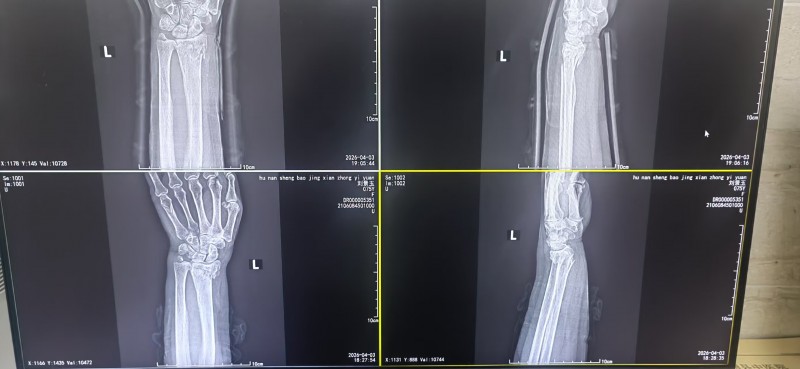

当天,刘女士被家人送到保靖县中医院。骨伤二科主任梁先海接诊后,诊断为柯雷氏骨折(桡骨远端距关节面2-3厘米骨折)。考虑到刘女士希望保守治疗,梁先海在仔细体查和阅片后,为她制定了局麻下中医手法正骨的个性化方案:先理筋,再采用“一拉二抖三屈掌四尺偏”的中医正骨手法复位,随后外用中药涂擦、自制硬膏外敷,并用自制小夹板固定,最后检查血运和手指活动。“一根自制小夹板、几双巧手,不用开刀,无需钢钉,就能将错位的骨骼复位如初。”刘女士说。

在保靖县中医院骨二科,这样的场景并不鲜见。梁先海介绍,对于桡骨远端骨折、前臂尺桡骨双骨折等骨科疾病,中医通过正骨、小夹板固定等非手术方法,常能达到与西医手术相当的疗效,且费用更低。自2025年保靖县师承湘潭市中医院正骨科主任曹谦教授以来,医院专门设立了中医正骨科。2025年全年接诊的100多例此类骨折患者,均通过中医正骨实现复位,基本未再实施切开复位内固定手术。